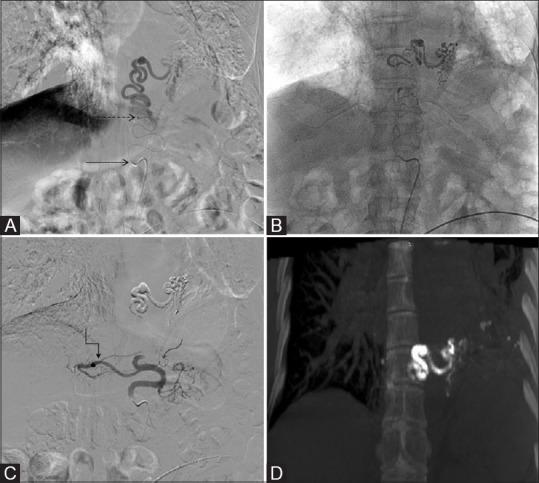

Dealing with technical challenges in embolization of a rare aberrant left inferior bronchial artery arising from the left gastric artery in a patient with massive hemoptysis.

Bronchial artery embolization is an established intervention for management of recurrent massive hemoptysis in a majority of patients. The source of bleeding in a majority of cases is systemic arteries - orthotopic bronchial arteries, anomalous bronchial arteries, or nonbronchial systemic collaterals. We report a case of an aberrant left inferior bronchial artery arising from the left gastric artery (LGA) in a patient with massive hemoptysis. Such origin from infradiaphragmatic vessels and specially left gastric arteries is very rare and needs to be considered by interventional radiologists and pulmonologists in case with hemoptysis disproportionate to supply by orthotopic arteries. Technical challenges were present in the present case in the form of an aneurysm in the aberrant artery and nontarget hepatic and gastric branches arising from LGA. Appropriate selection of hardware and embolic agents was done to deal with the clinical situation.